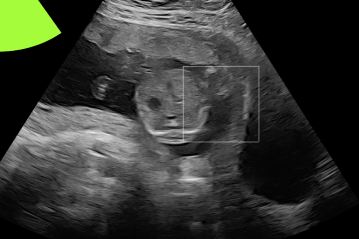

Three in vivo Bmode fetal images with and without aberration correction are presented in Figs. 10-12. GIF images of examples A-L (see Fig. 9 and Table 5) alternating between the corrected and uncorrected images are uploaded as supplementary material. The differences in image quality are easier to appreciate in the GIFs than in a side-by-side comparison. The data points for the three examples are colored black in Fig. 9. Table 5 give tabular values for the global sound speed estimate, sharpness increase (κ𝜅\kappa) and answers from the clinical evaluations.

Figure 11: Example B. In vivo fetal Bmode image using constant 1540 m/stimes1540dividemetersecond1540\text{\,}\mathrm{m}\text{/}\mathrm{s} and the estimated average sound speed map. The average sound speed map is shown in the top right corner and the rightmost colorbar indicates the sound speed values. Alternating GIFs are found in the supplementary material.

The in vivo examples A-C, in Figs. 10-12 respectively, show different nuances of how sound speed aberration correction improves focusing quality. A noticeable improvement in Fig. 10 is the improved contrast and clarity of borders. The sound speed correction seems to remove the double structure indicated by the arrows in Figs. 10c-10d. The skull border and the brain structures in Fig. 11 are also better defined and clearer after aberration correction. Example C in Fig. 12 is the image with the highest increase in Tenengrad κ𝜅\kappa, seen from Fig. 9 and Table 5. The improvement in image quality is evident around the boundary of the fetus body and the correction sharpens the structures indicated by the arrows. The improved contrast between the layers in the shallow tissue layers is also noticeable.